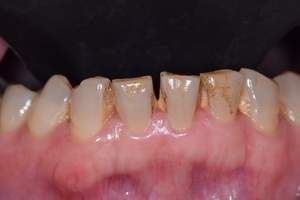

歯石除去

治療前

治療後

| 年齢 | 36歳・男性 |

| 主訴 | 歯石をとりたい |

| 治療内容 | 歯石除去 |

| 治療期間 | 30分 |

| 費用 | 約2,000円 |

| リスク・副作用 | ・歯ぐきの炎症が強いと歯石を取る際に出血することがあります。 ・処置後に歯がしみることがあります。 ・歯と歯の間に隙間ができるので、息が漏れ発音しにくいと感じることがあります。 ・歯ぐきの炎症が軽減すると歯ぐきが引き締まり、歯が長く見えることがあります。 |